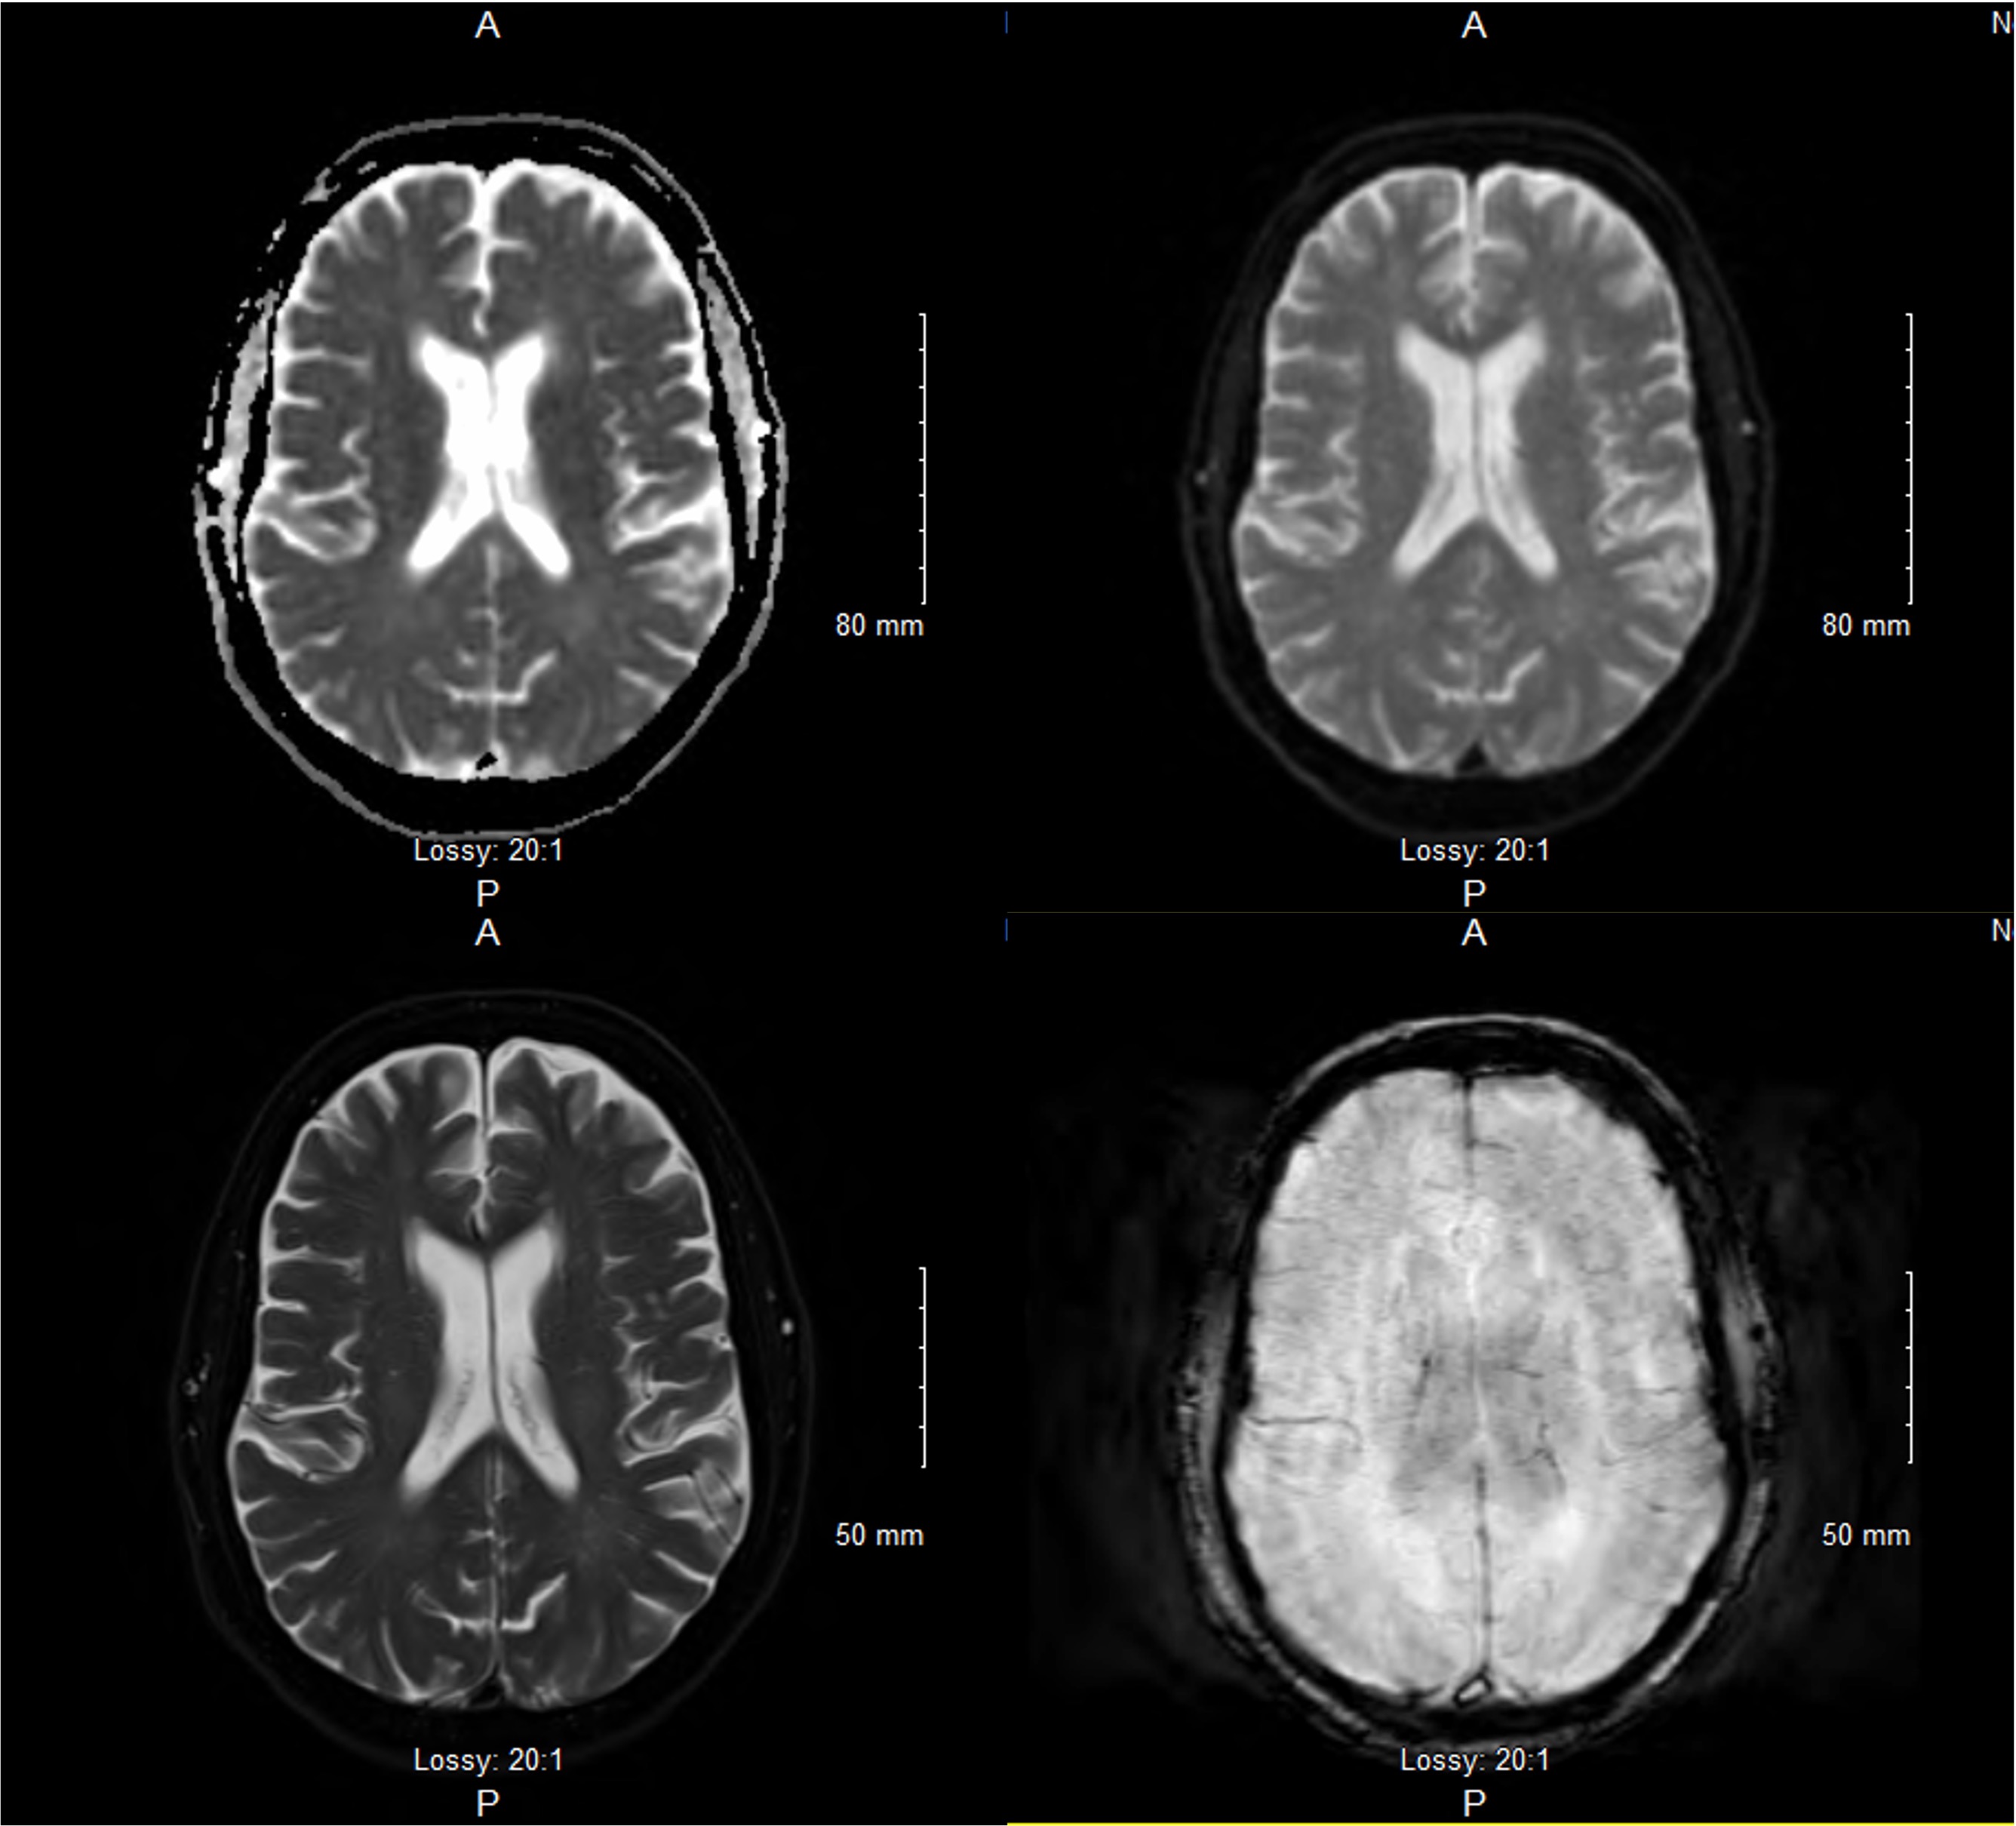

Figure 2. Brain MRI, transverse view, showing only mild chronic microvascular changes

Initial workup with CBC, CMP, ESR, CRP, viral panel, head CT, MRI of the brain and neck were unremarkable. A video and barium swallow confirmed severe dysphagia and patient was kept NPO. Differentials included Miller Fisher Variant of Guillain-Barre Syndrome (GBS) and MG.